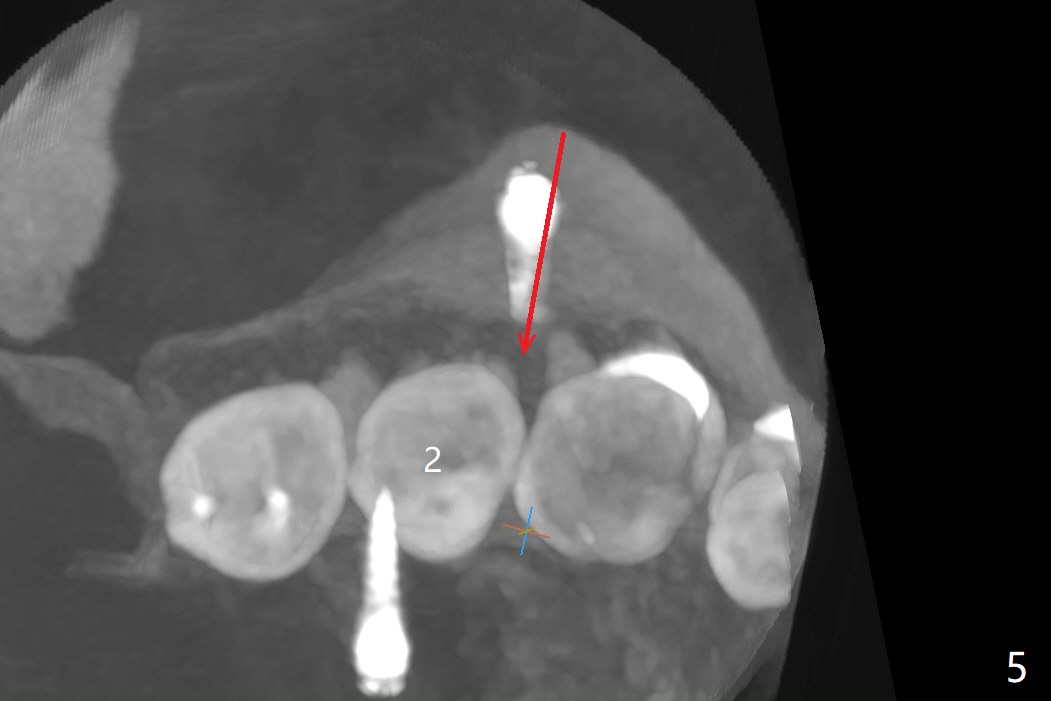

When 6 and 8 mm Tomas pins are initially placed mesiobuccal (MB) and distolingual (DL) to the supraerupted tooth #2, PA is taken (Fig.1), which shows that the DL one seems too distal. The mini implant is removed and placed more mesial (Fig.2, 7 (^: original entry)). When the patient experiences a little pain as the DL implant is being placed deeper with minimal local anesthetic, CT is taken. In fact the latter is between the apices of the teeth #1 and 2 (Fig.3 (L: lingual view of 3D image)). The implant is later placed deeper with minor angular change as well as more anesthetic. There is an advantage to place the miniimplants apically; there is more space. But the MB implant is a little bit mesial (Fig.4). After withdrawal, the trajectory of the implant is changed somewhat as indicated by a red arrow in Fig.5). Note the apical placement of the minimplants (close to mucogingival junction, Fig.6,7).